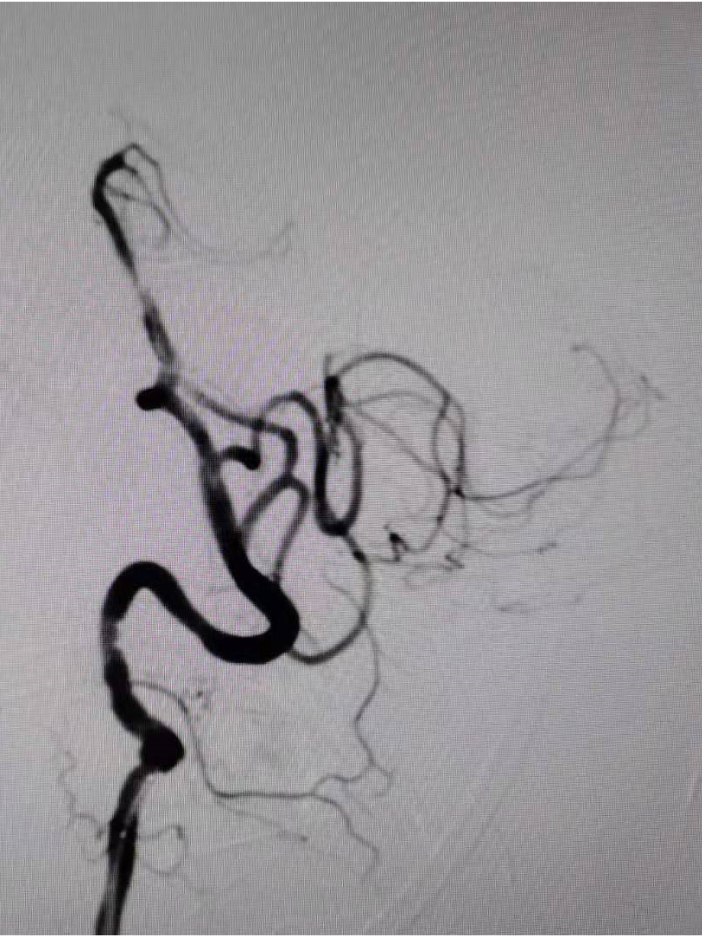

扩张后造影,提示恢复正向血流,残余狭窄50%左右。发现加奇SacSpeed® 2.5mm×9mm颅内球囊扩张部位存在双腔征,考虑血管夹层,给予替罗非班8ml/h持续泵入。

通过长交换技术,将XT-27定位在右侧大脑后动脉P2段,将Neuroform颅内支架3.5×15mm,定位在基底动脉狭窄处。

释放支架。

病人的选择:颅内动脉闭塞再通一定要选择有症状的,标准药物治疗欠佳病人。如果是前循环,可以术前完善灌注成像,选择失代偿的病人。最好选择近期闭塞的病人,时间越长斑块越硬,血管床破坏越重,开通成功率越低。有时不好判断闭塞时间,患者近期有缺血事件发生,提示有可能近期发生闭塞。闭塞节段最好不要超过15mm,有时可以通过高分辨磁共振对闭塞节段的长短和血管床情况进行评估。该病人因为有吻合血管,远端血管床显影,可以直接判断闭塞节段不超过15mm。